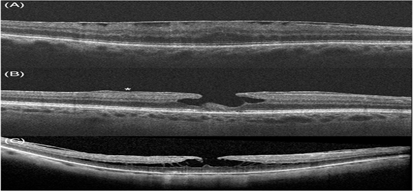

Hình ảnh trên OCT của màng trước võng mạc và các khái niệm có liên quan: A- màng trước võng mạc, B- lỗ lớp hoàng điểm cùng với tăng sinh trước võng mạc (dấu sao), C- tách lớp VM

Sự thay đổi từ phương pháp soi sinh học bằng đèn khe truyền thống sang phương pháp chụp ảnh cắt lớp võng mạc thế hệ SD-OCT đã dẫn đến nhu cầu sửa đổi các định nghĩa lỗi thời về các bệnh võng mạc vốn có thể khó phân biệt với nhau. Giờ đây các bác sĩ có thê phân định chính xác các tổn thương sau đây với nhau:

- Màng trước võng mạc

- Tăng sinh trước võng mạc

- Lỗ lớp hoàng điểm

- Tách lớp võng mạc vùng hoàng điểm- Foveoschisis